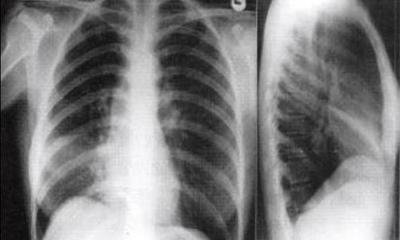

流感主要通过飞沫传播,也可通过接触传播,其中,孕妇、婴幼儿、老年人和慢性基础疾病患者是高危人群,患流感后出现严重疾病和死亡的风险较高。如怀疑自己感染了流感病毒,可通过血液检查、病原学检查和影像学检查来进行诊断。